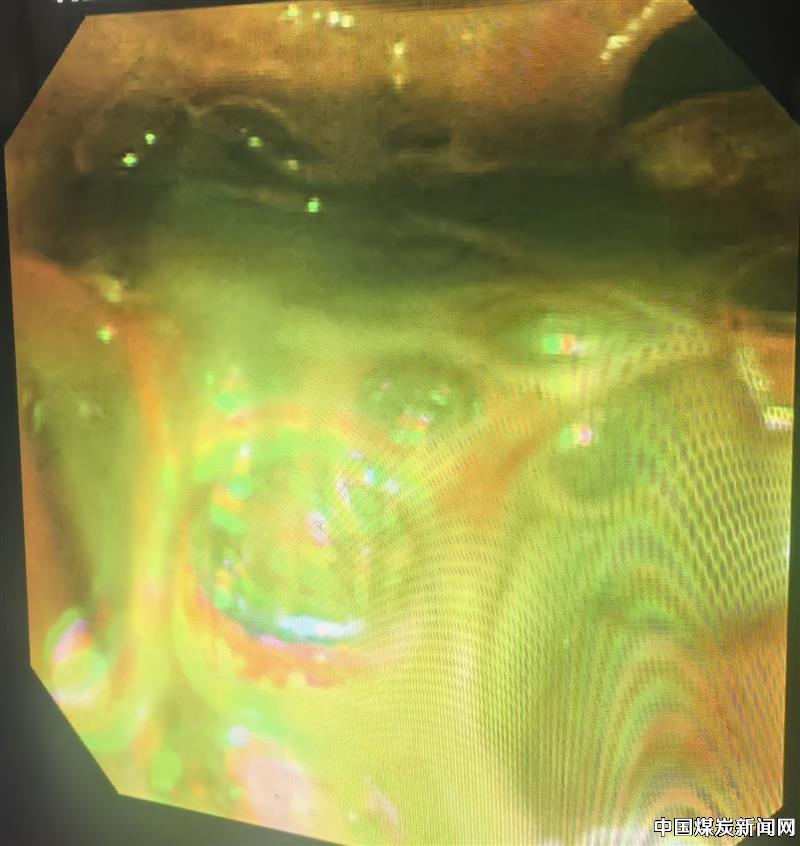

患者85岁,不仅基础疾病多,还伴有感染性休克、酸碱平衡紊乱、电解质紊乱、低蛋白血症等,均增加了手术风险。救与不救风险都很高,面对这样的两难问题,刘大夫、李主任会商后决定冒险一搏。经过耐心向患者家属交代病情及手术风险,并取得同意后,急诊行ERCP术。术中见大量脓液流出,证实了术前诊断,手术过程顺利,术后患者病情逐步恢复正常。